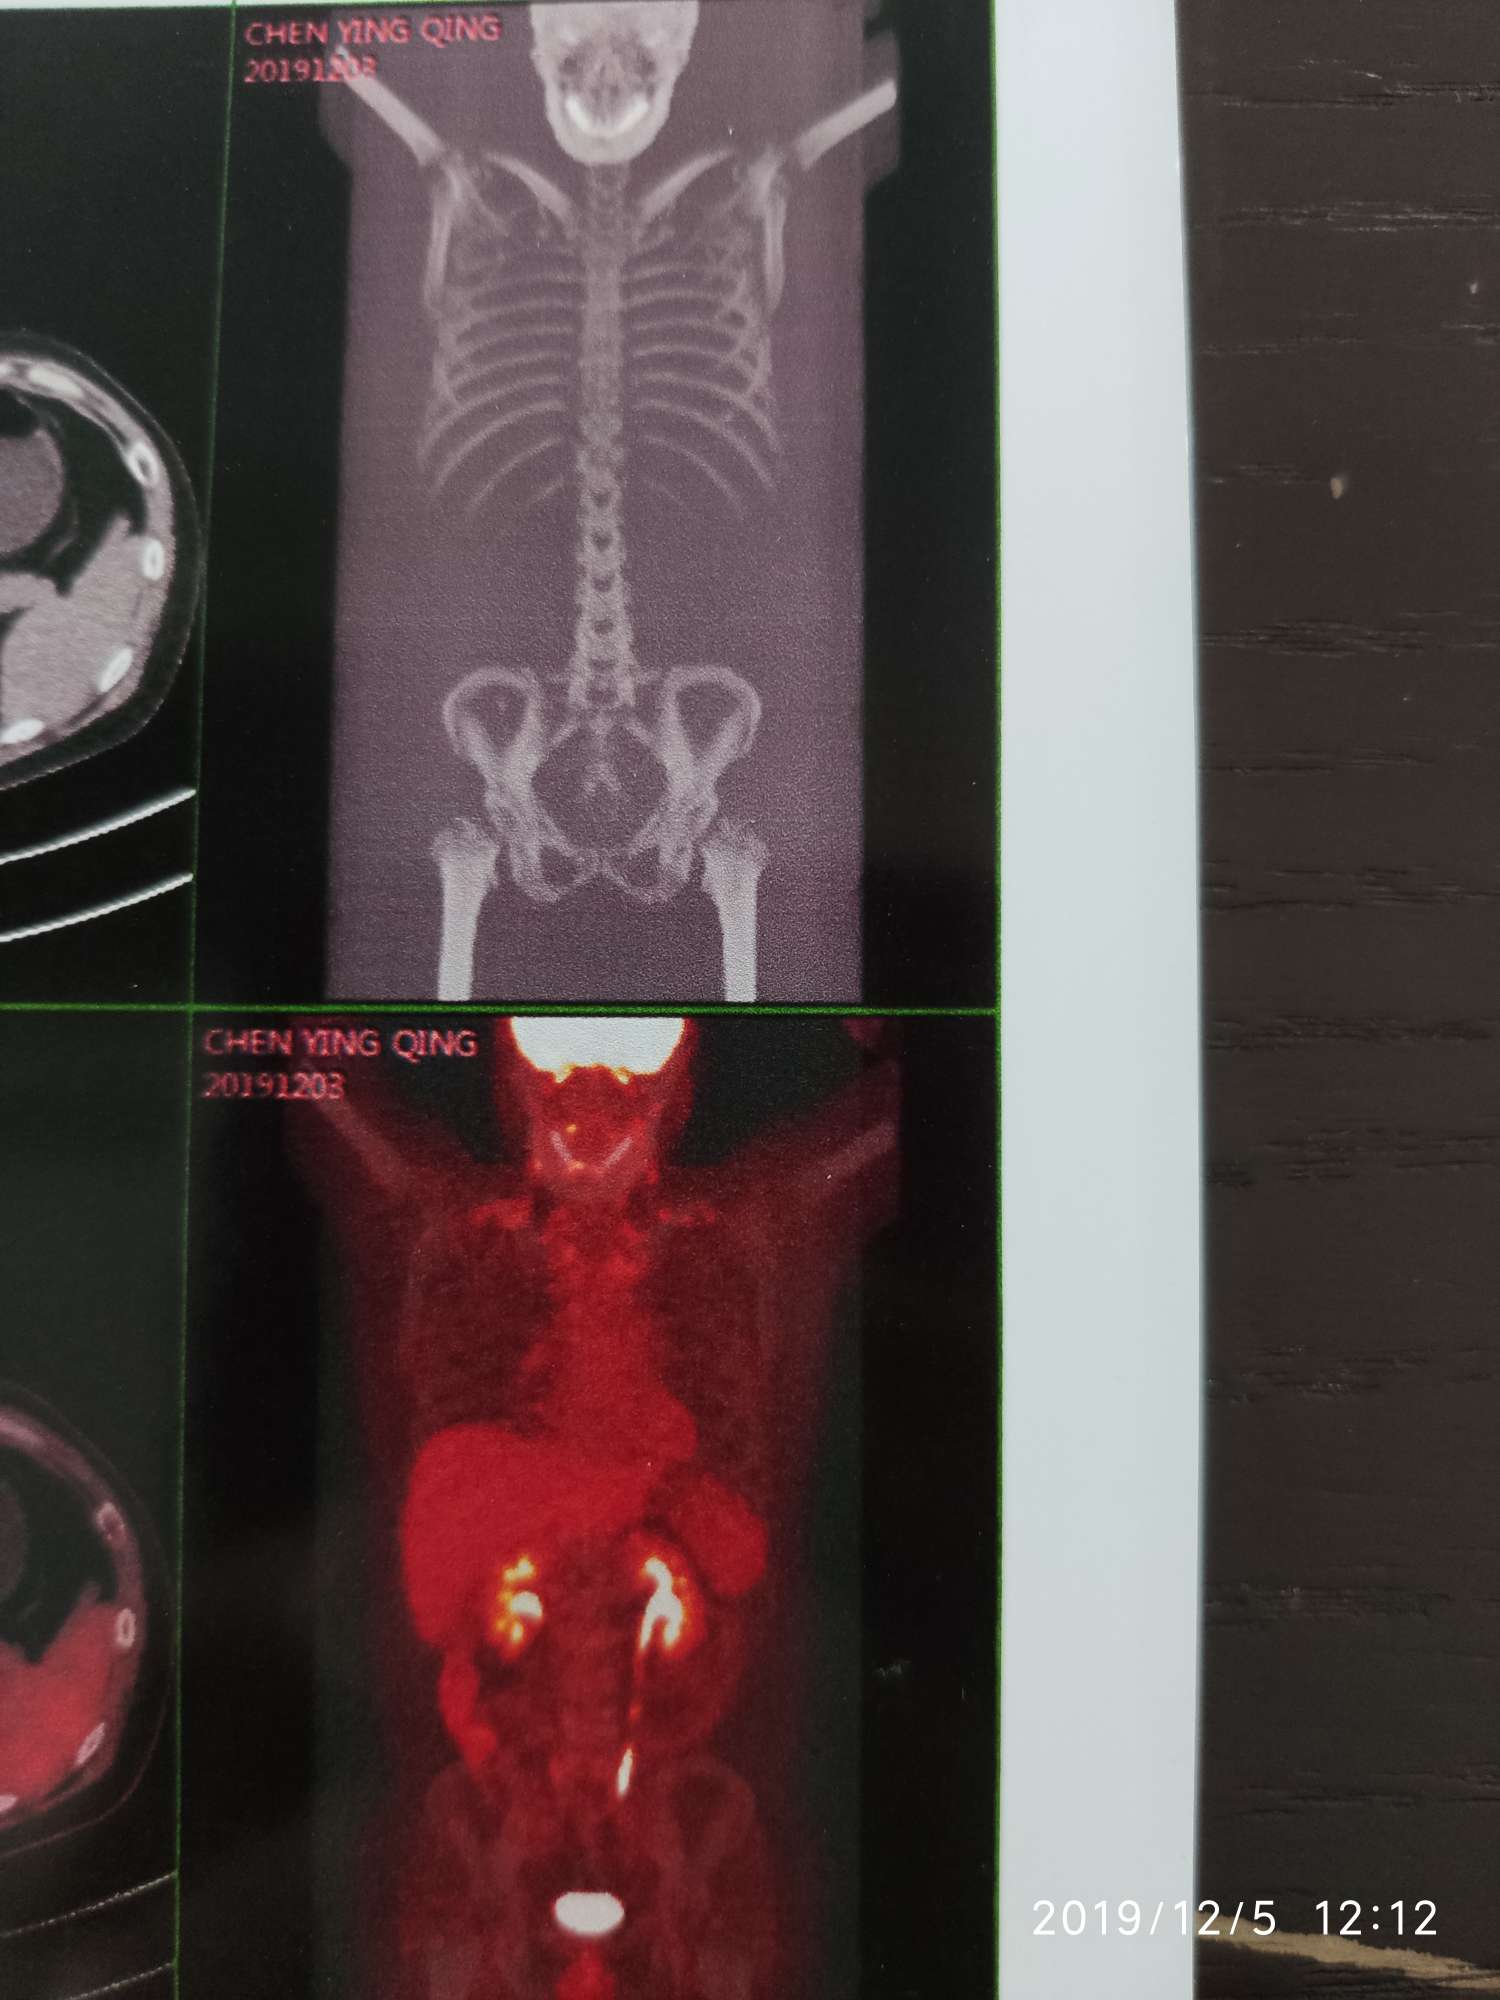

这是前两天的检查结果

12月petct检查,全身未发现有高摄取病灶,骨转部位密度增加,医生结论可能癌细胞被抑制,医生建议继续泰瑞莎单药治疗,后续再复查,结果好的话可以考虑停药。